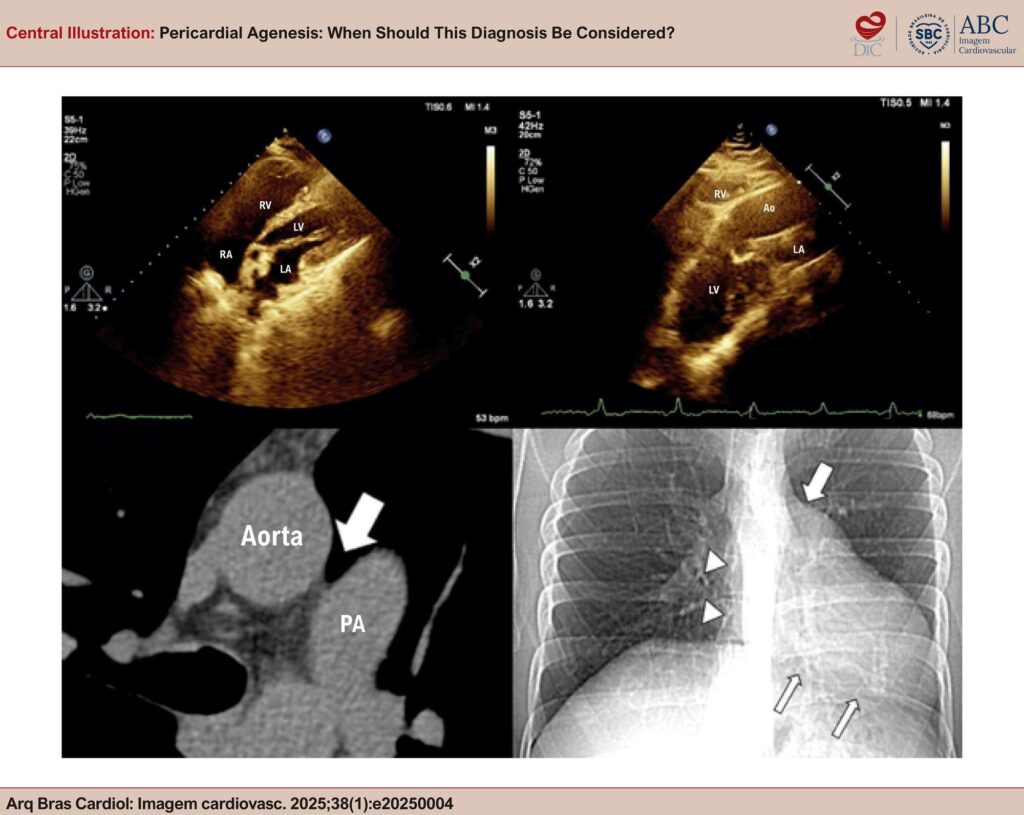

Central Illustration

: Pericardial Agenesis: When Should This Diagnosis Be Considered?